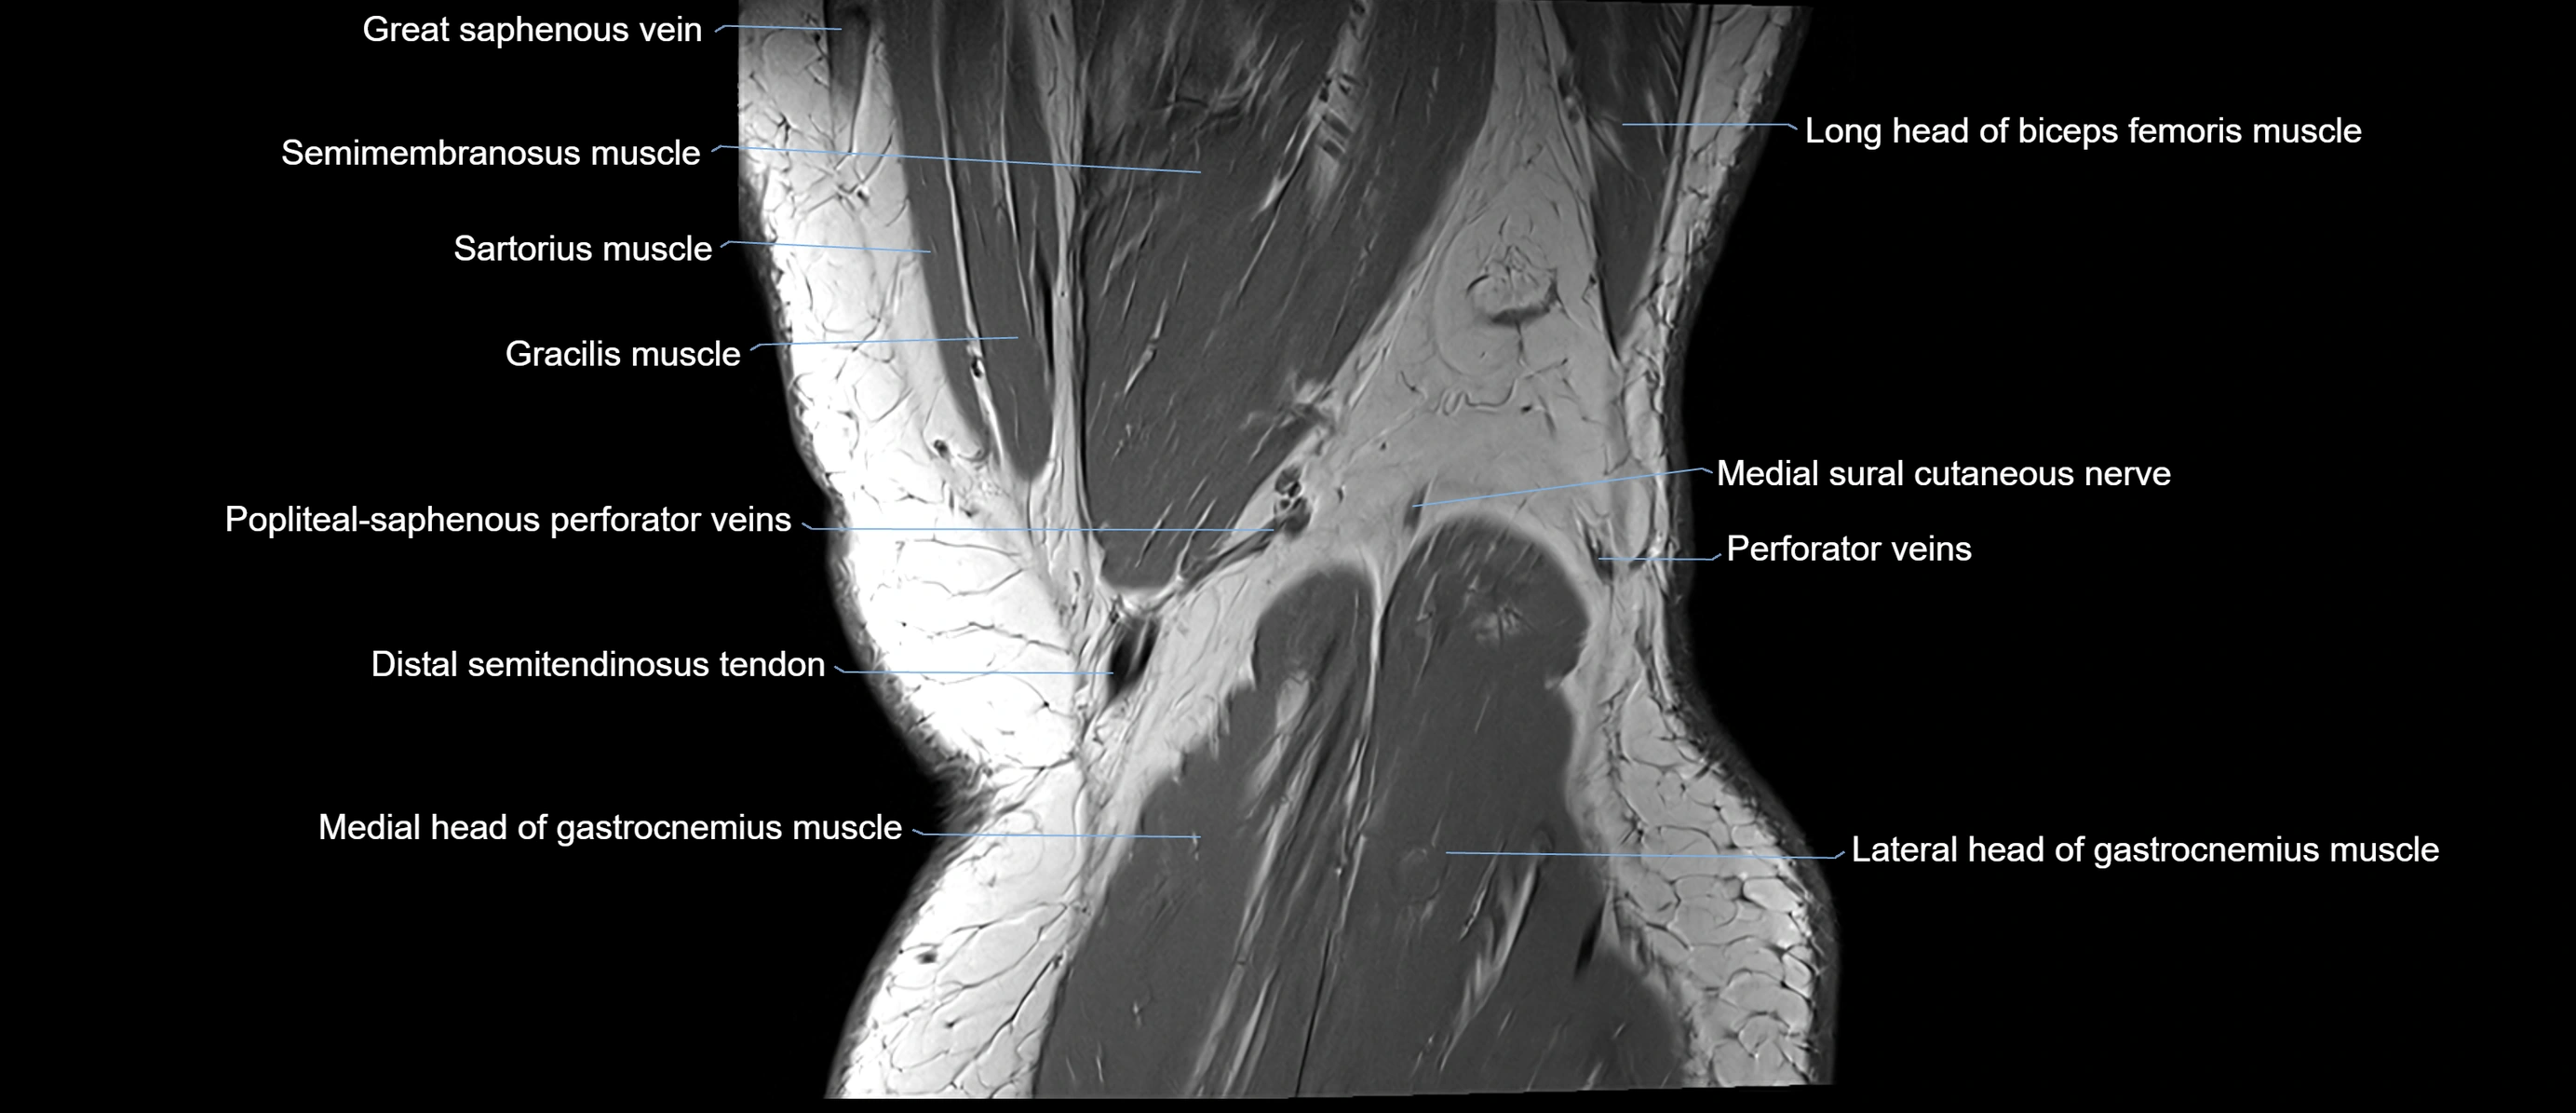

- Biceps femoris muscle (Long head)

- Distal semitendinosus tendon

- Medial head of gastrocnemius muscle

- Medial sural cutaneous nerve

- Popliteal–Saphenous perforating veins

- Sartorius muscle

- Semimembranosus muscle

- Semitendinosus muscle

- great saphenous vein